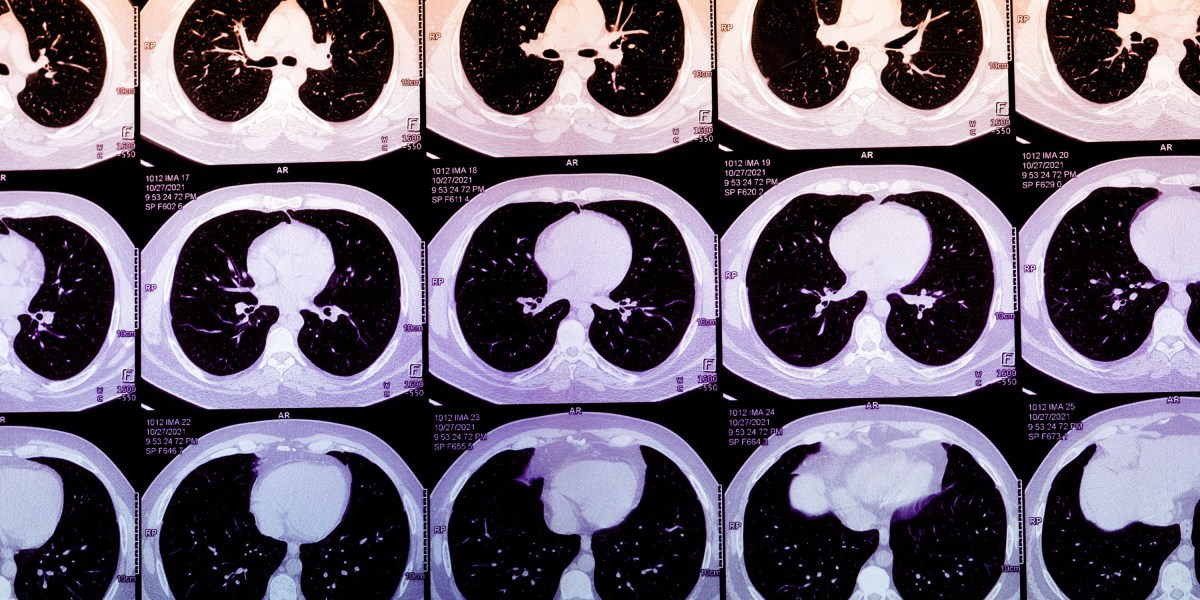

Coronary artery calcium can often be spotted on chest CTs, and its concentration can be subjectively described. Normally, quantifying a person’s CAC score involves obtaining a heart-specific CT scan. Algorithms that calculate CAC scores from routine chest CTs, however, could massively expand access to this metric. In practice, these algorithms could then be deployed to alert patients and their doctors about abnormally high scores, encouraging them to seek further care. Today, the footprint of the startups offering AI-derived CAC scores is not large, but it is growing quickly. As their use grows, these algorithms may identify high-risk patients who are traditionally missed or who are on the margins of care.